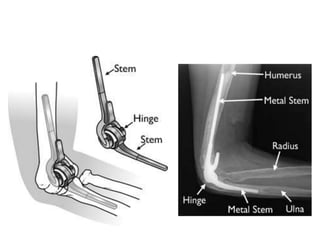

Total elbow arthroplasty

• Semiconstrained hinge design is used to treat

unsalvageable nonunions.

• All the previous implants are removed and

arthroplasty is proceeded.